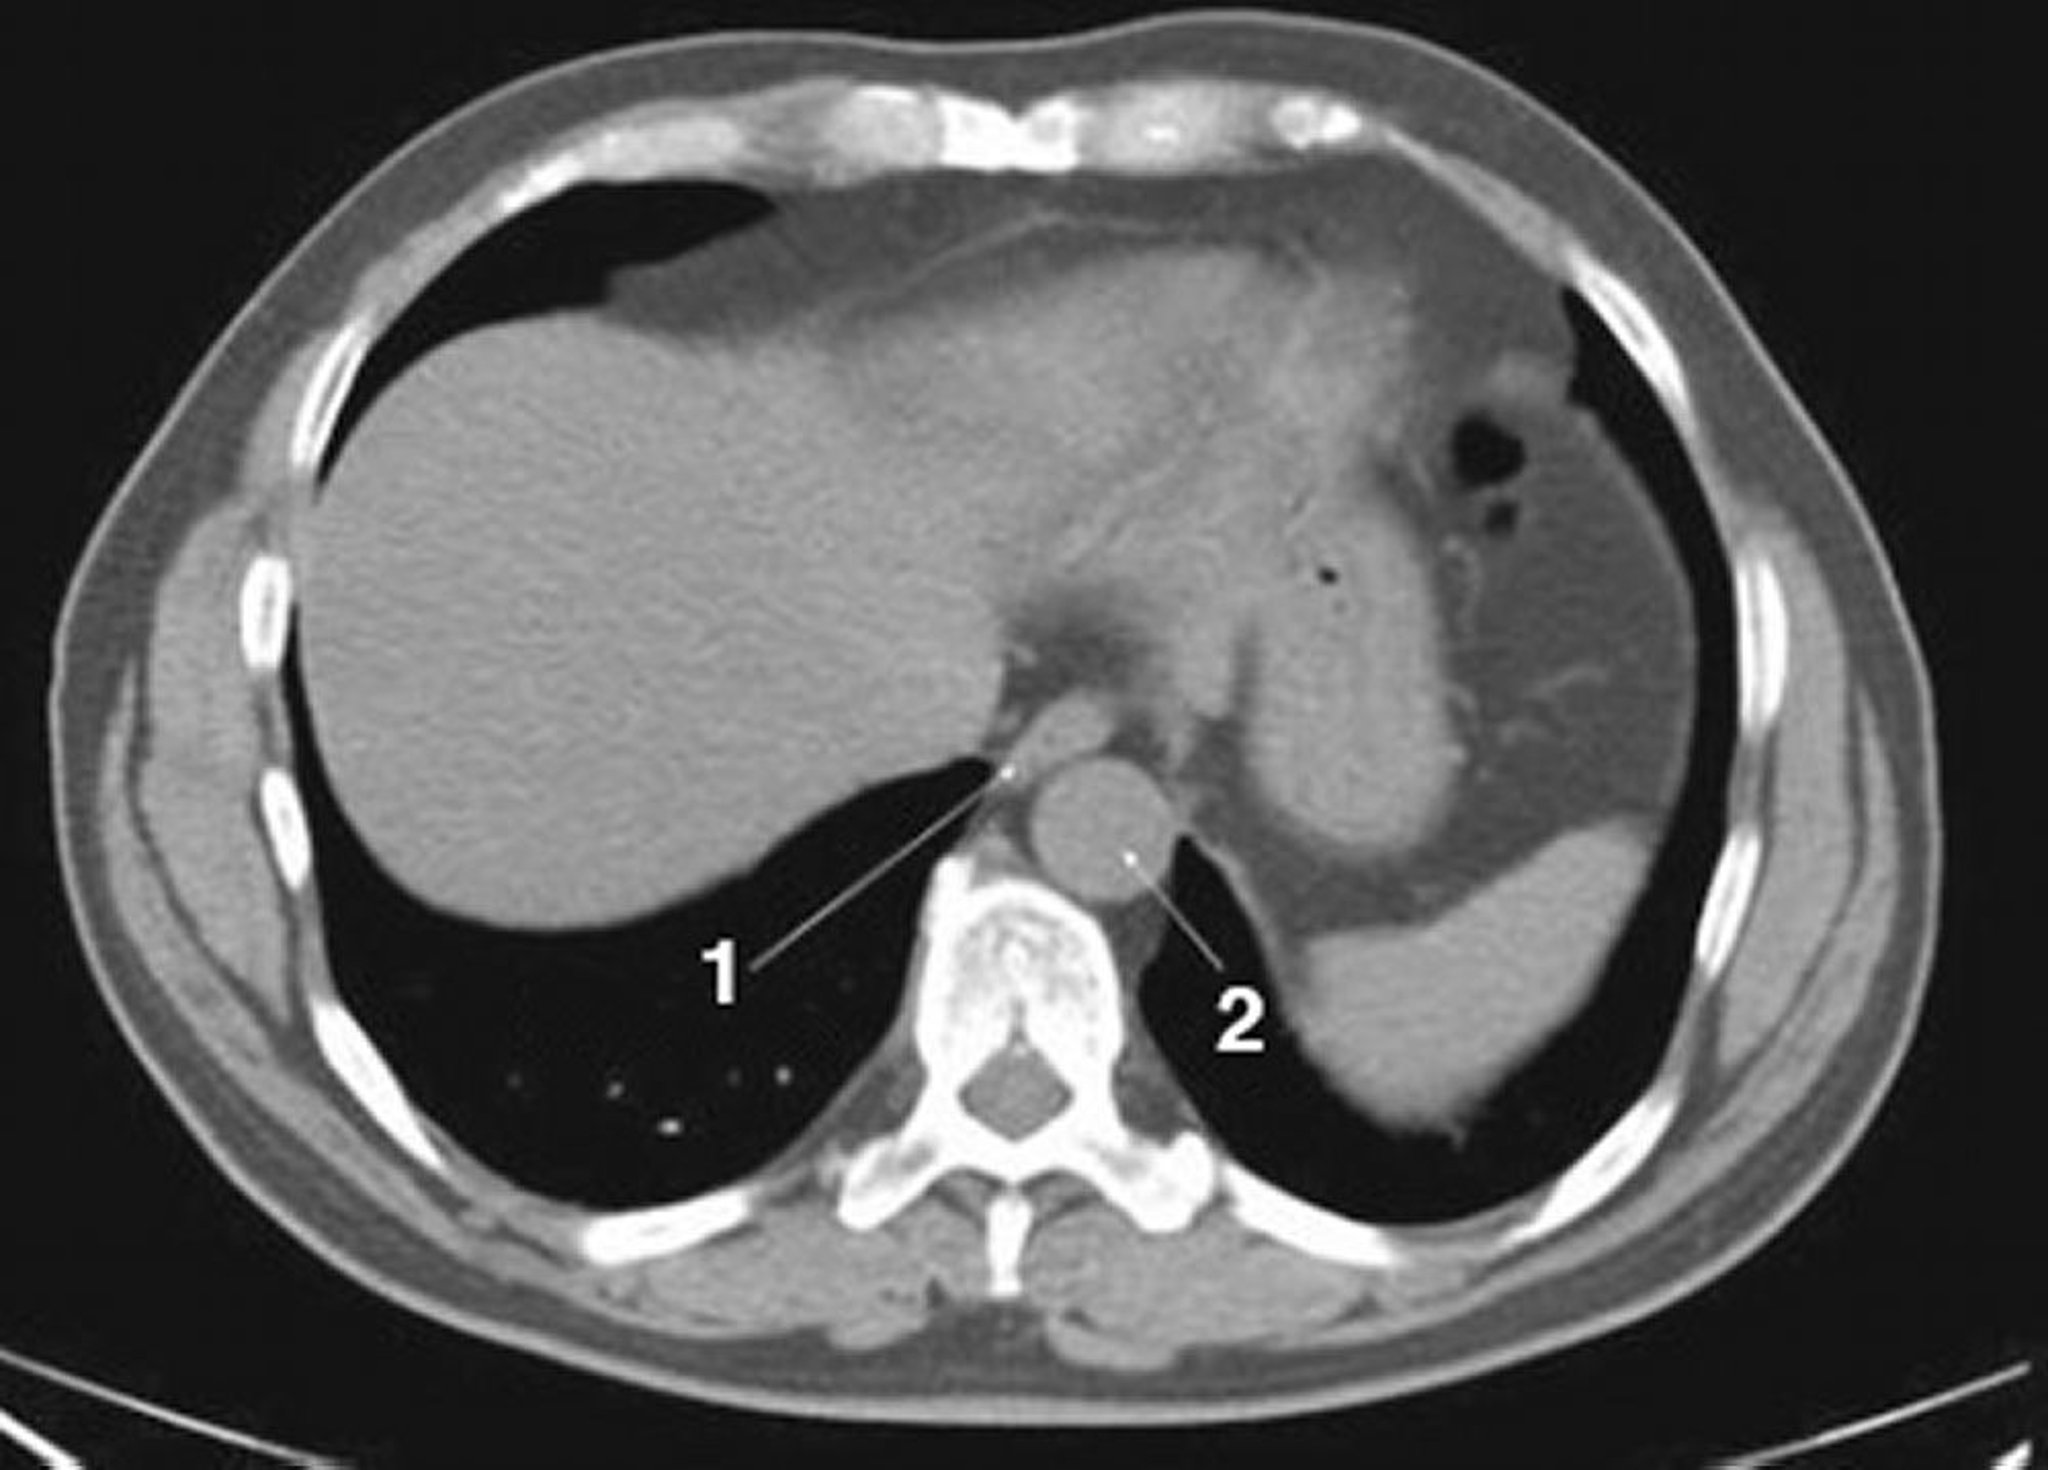

TC senza contrasto dell'addome e della pelvi che mostra un'anatomia normale (Slide 1)

1 = esofago; 2 = aorta.